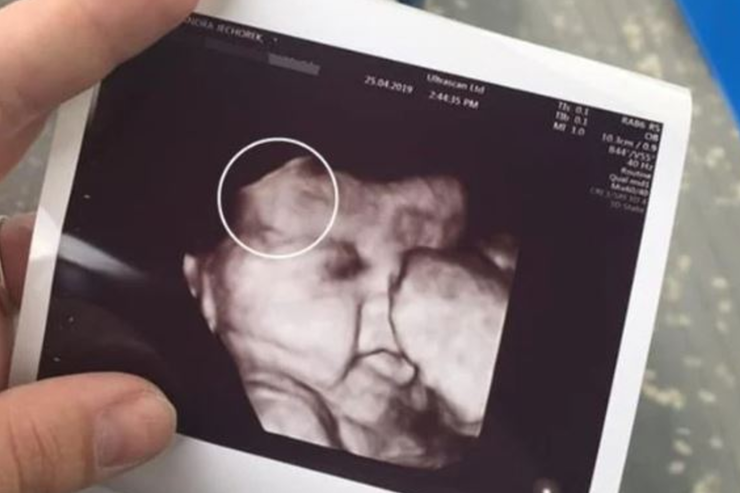

Alexandra es el nombre de la joven de 21 años oriunda de Irlanda que causó emocionantes reacciones desde que su hija nació a mediados de 2019. Si bien esta era su segunda hija, lo cierto es que la especial atención hacía la cabeza hacía comenzado en la semana 34. Fecha en la que, tras una ecografía, se comenzaba a notar su voluptuoso pelo.